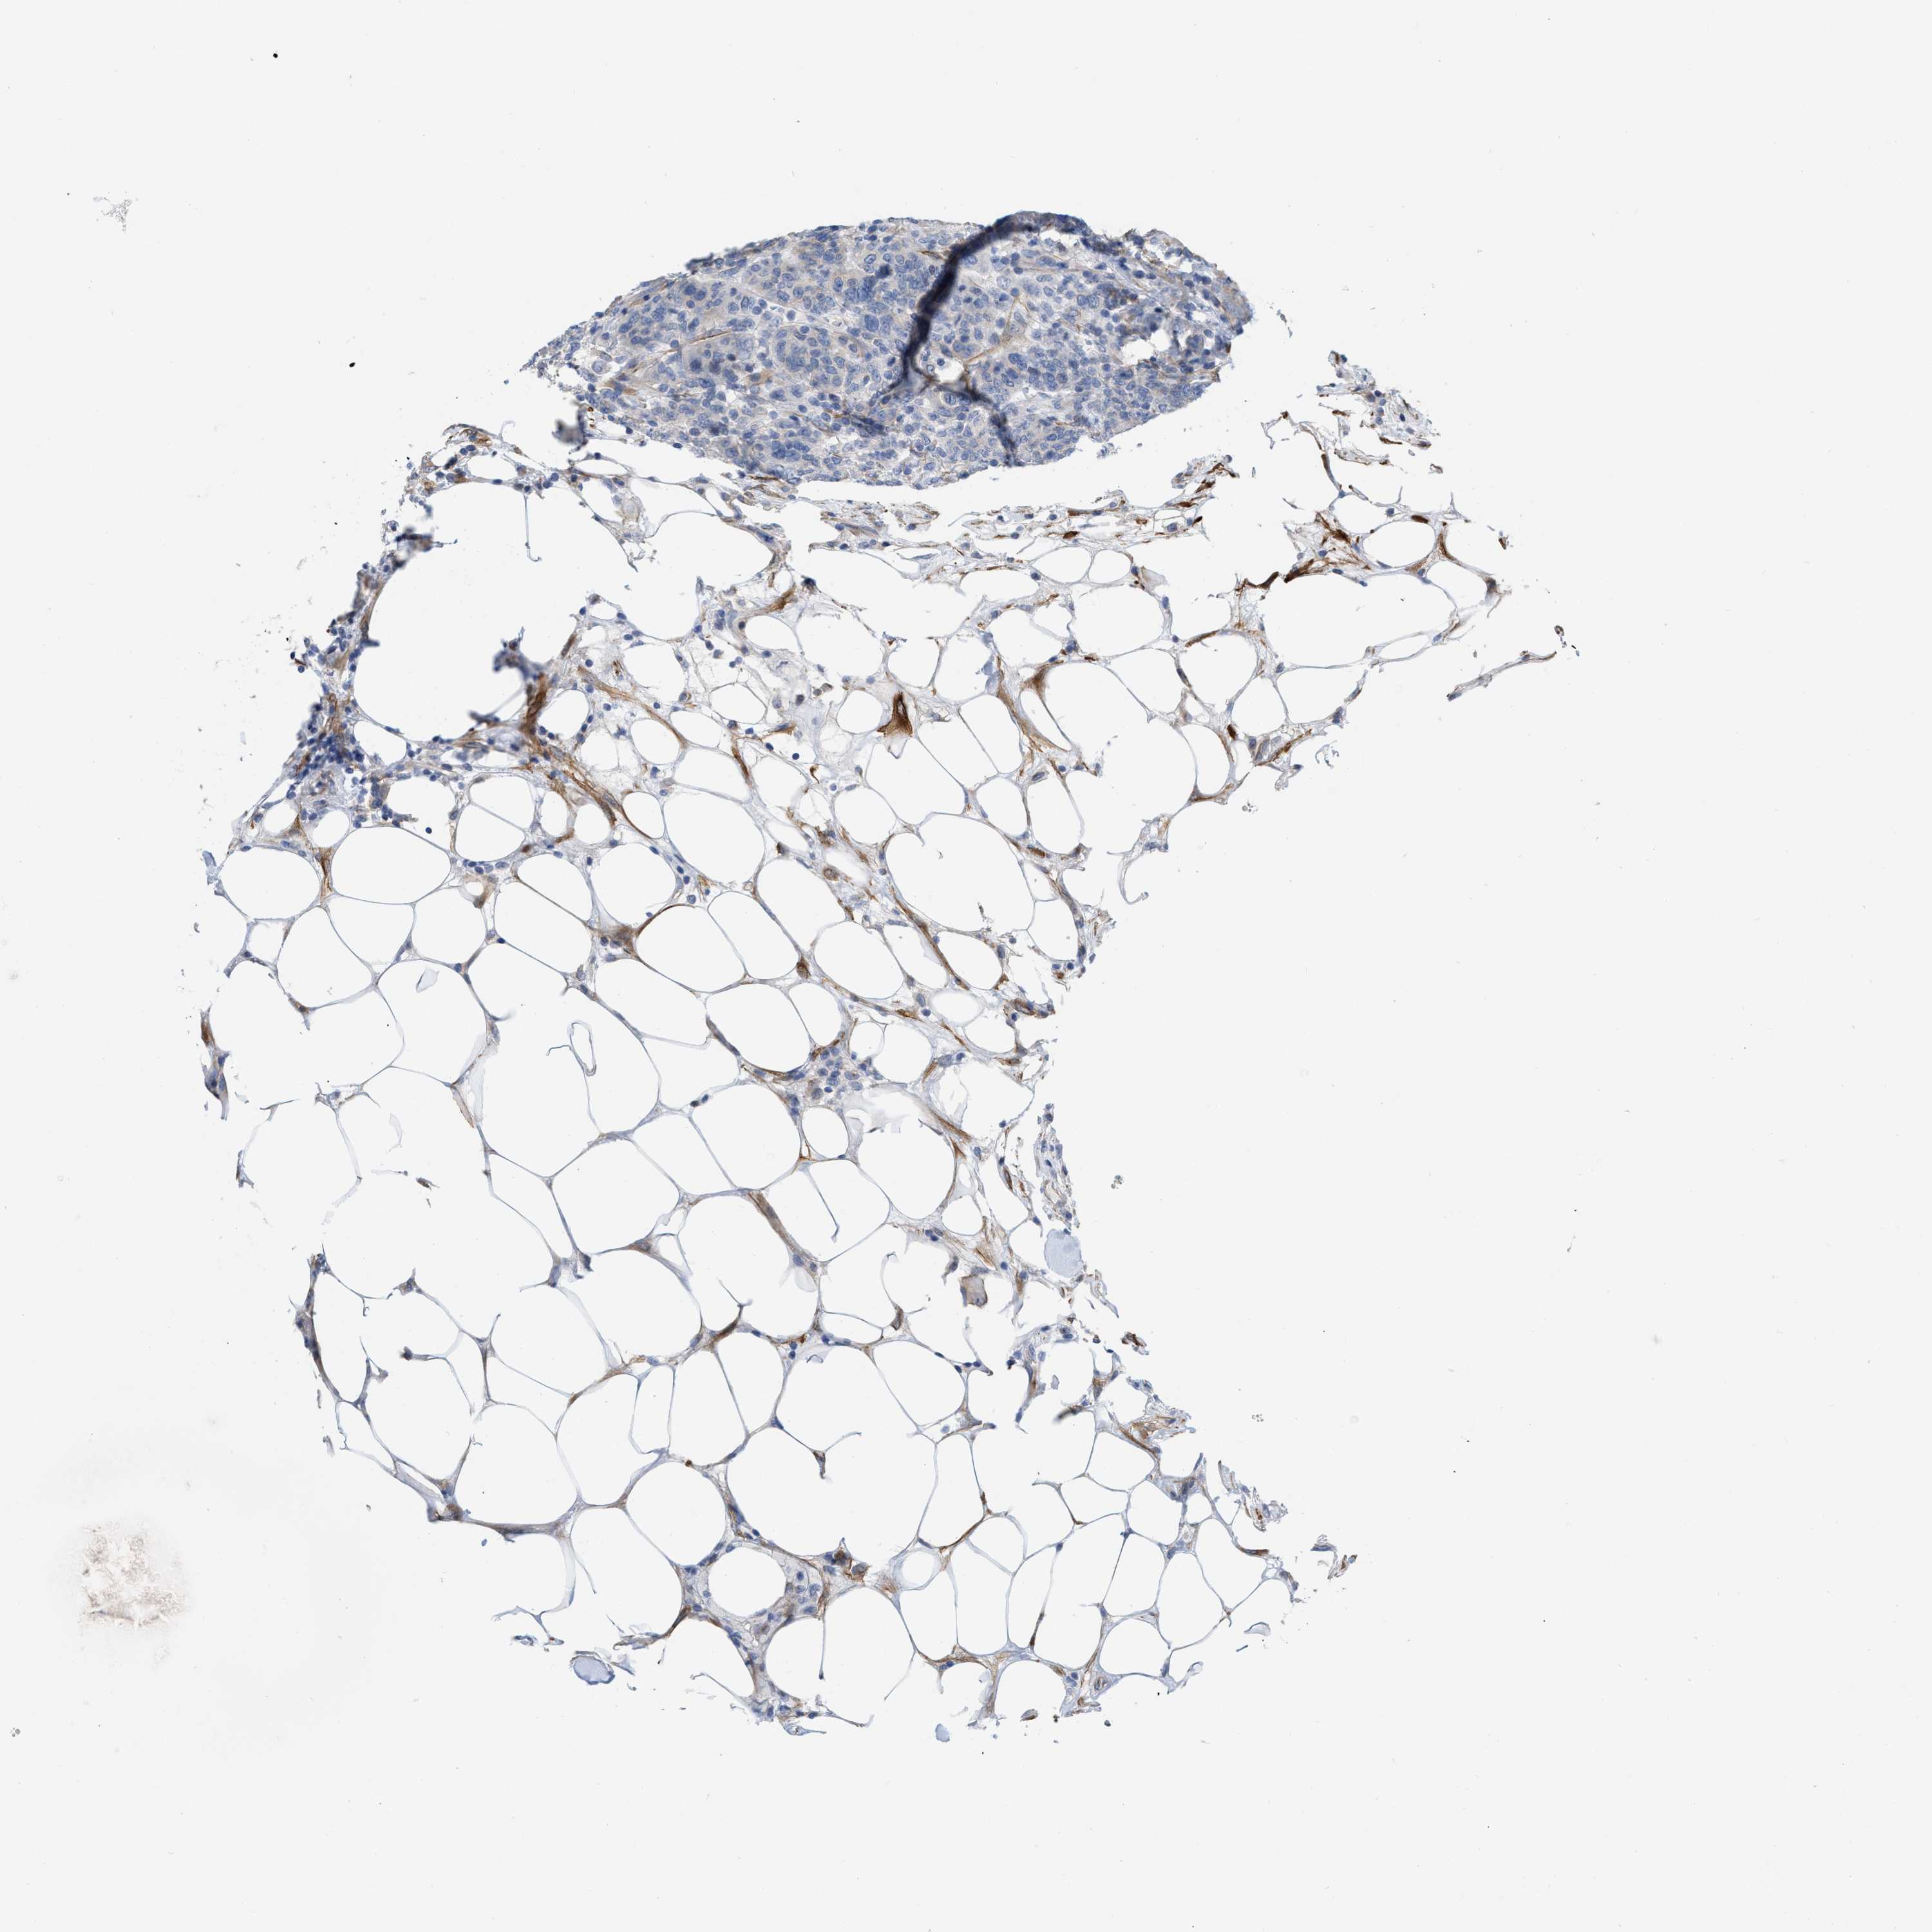

BRCA TCGA BRCA VALIDATION PROTEIN EXPRESSION

ANTIBODIES

AND

VALIDATION